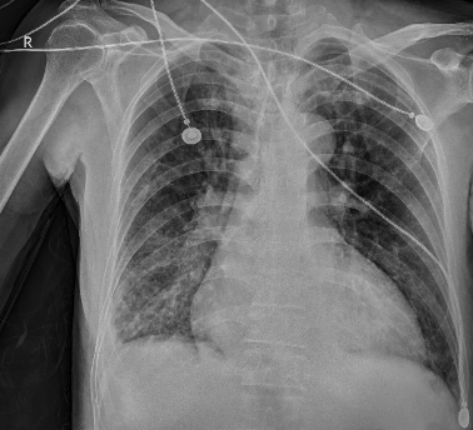

急诊床旁胸片(图1):右肺中下野炎症,右侧胸腔少量积液;心影形态增大,主动脉迂曲伴壁钙化108床边心超检查左室射血分数约30%,左室偏大,心功能不全轻中度三尖瓣关闭不全;床旁双下肢血管彩超双侧下肢动脉点状斑块形成双侧下肢深静脉血流通畅

图片

1  急诊床旁胸片2025-10-07